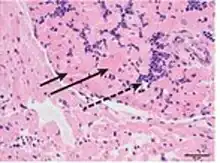

a-c)Clinical manifestations of Lujo haemorrhagic fever, including facial and neck swelling, subconjunctival haemorrhage , and maculopapular rash